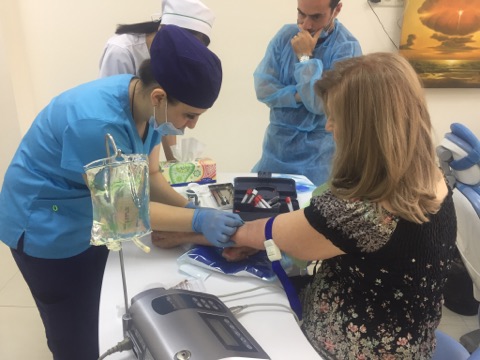

Мастер-класс начался с обсуждения предстоящей операции и снимка компьютерной томографии, после чего участники смогли присутствовать на операции.